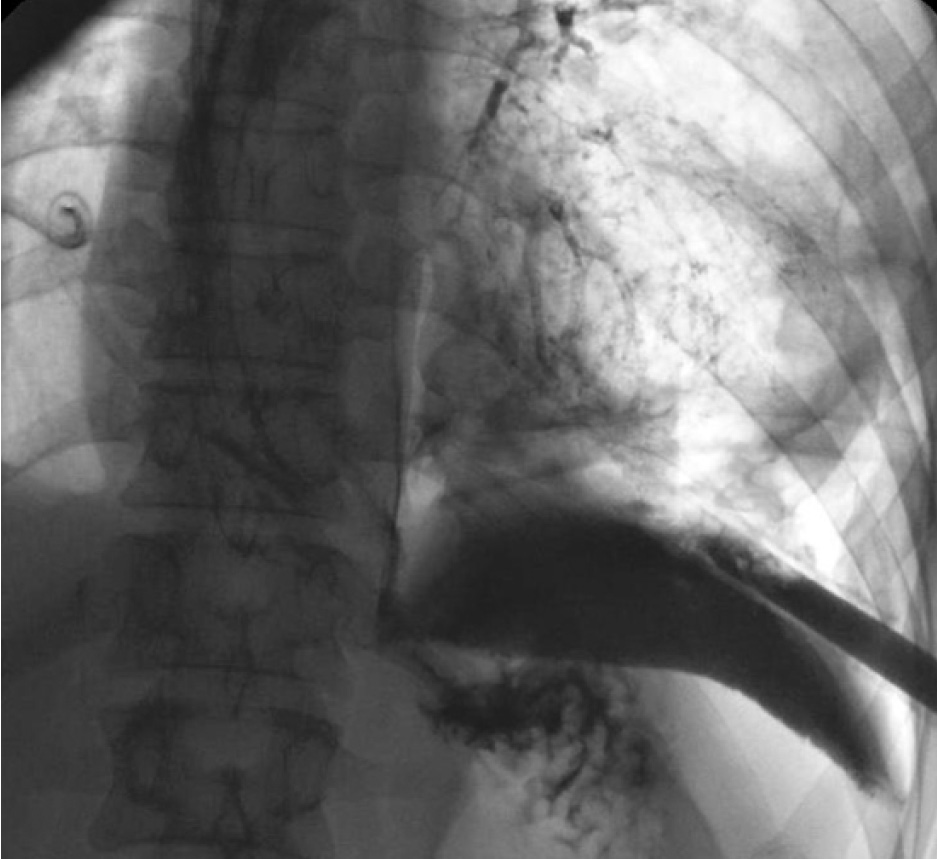

Медиастинальная плевра вскрыта на всем протяжении. Наложены двухрядные швы на стенку пищевода в продольном направлении. Линия швов укреплена плевральным листком. Средостение и плевральная полость дренированы толстыми трубками. В тонкую кишку установлен энтеральный зонд для питания. Ранний послеоперационный период протекал без особенностей. Однако на 4-е сут состояние больного резко ухудшилось: сознание на уровне оглушения, наросли признаки интоксикации и системной воспалительной реакции. По дренажам стало отделяться мутное содержимое с примесью желчи. При пероральной контрастной эзофагоскопии выявлен затек в обе плевральные полости (рис. 1). Констатирована несостоятельность швов пищевода.

Рис. 1. Рентгенконтрастное исследование пищевода. Затек контрастного вещества в левую плевральную полость